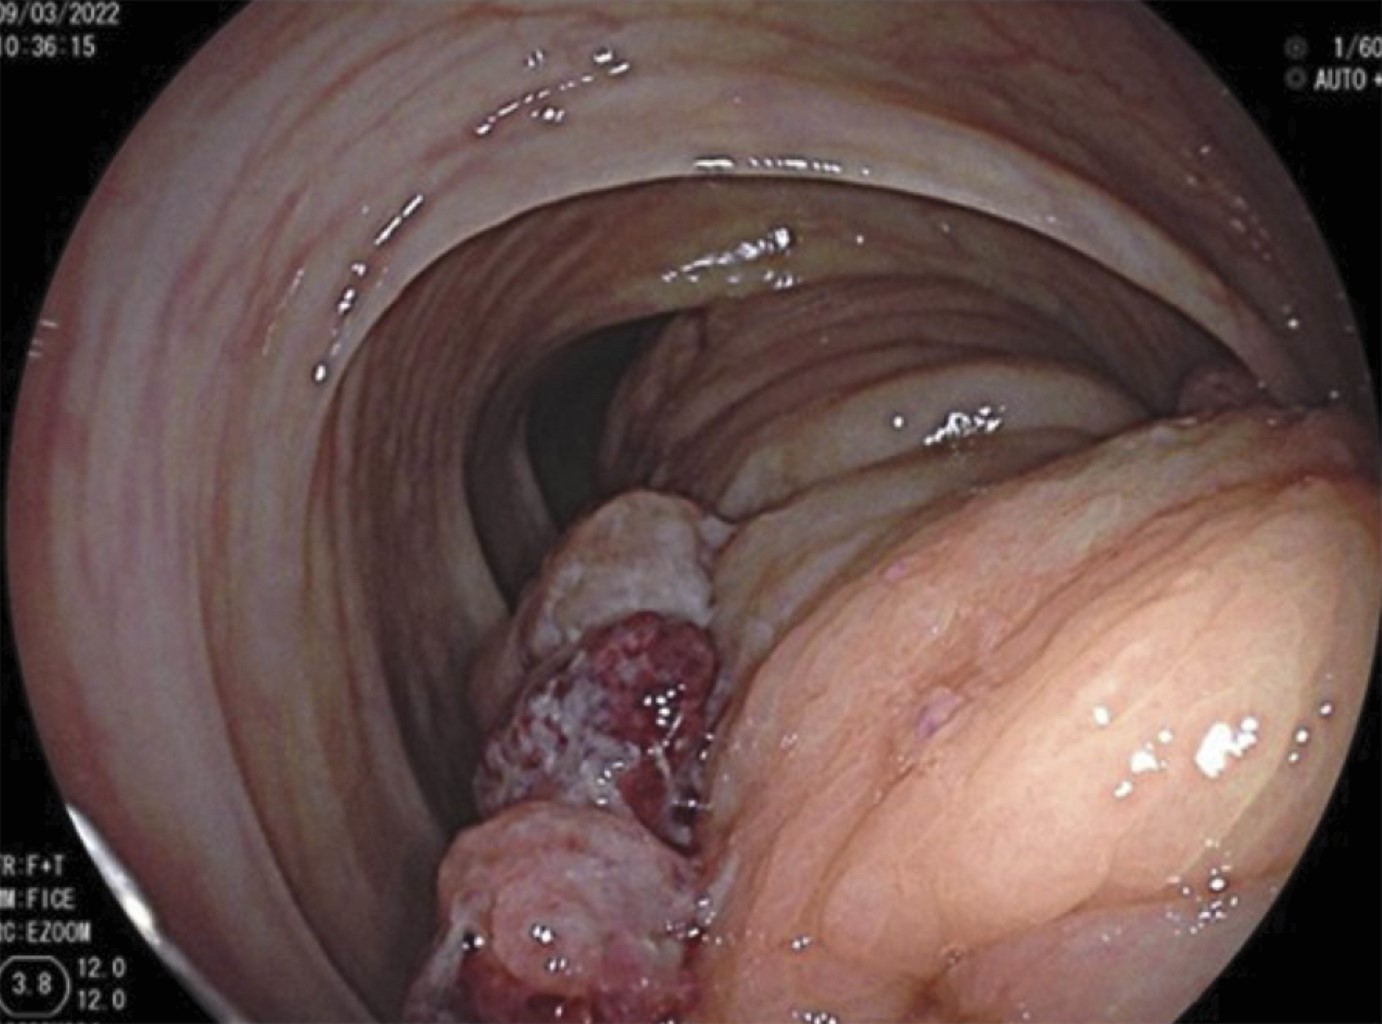

Figure 3